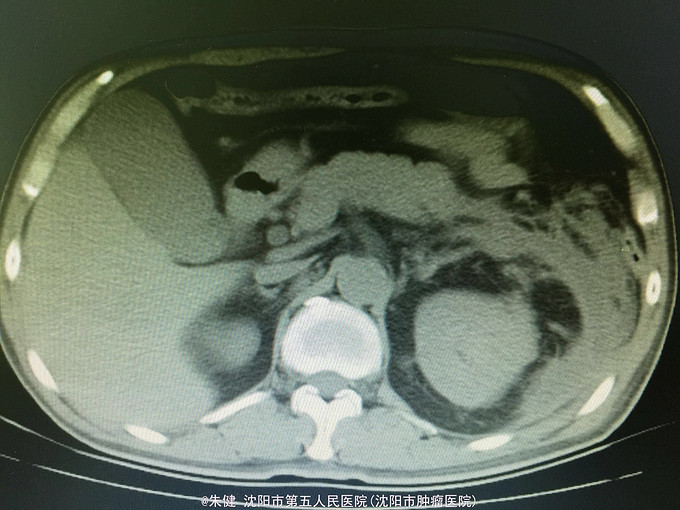

男,52岁 主诉:上腹部胀痛30小时, 现病史:30小时前饮酒后引起上腹部胀痛,持续性,逐渐加重,累及腰背部,恶心,呕吐数次胃内食物,无发热,未治疗,因不见好转来诊;病来无心悸、气短,排气、排便可,排尿正常。

一般状态可,腹部平坦,未见肠形及蠕动波,剑突下及左侧上腹部压痛,轻度肌紧张,未及包块,无移动性浊音,肠音正常,肾区无扣痛。 辅助检查:血常规:白细胞13.6*10^9/L,中性83.3/L;尿淀粉酶:214U/L,上腹部CT:左侧胸腔积液,左肺下叶可见斑片及索条状影;胆囊增大,胆道内未及结石影;胰腺形态及密度正常,胰腺尾部周围可见索条状影及积液影。

诊断:急性胰腺炎 处理:给予禁食、补液、抗炎及抑肽酶治疗,病情逐渐好转,一周后出院。